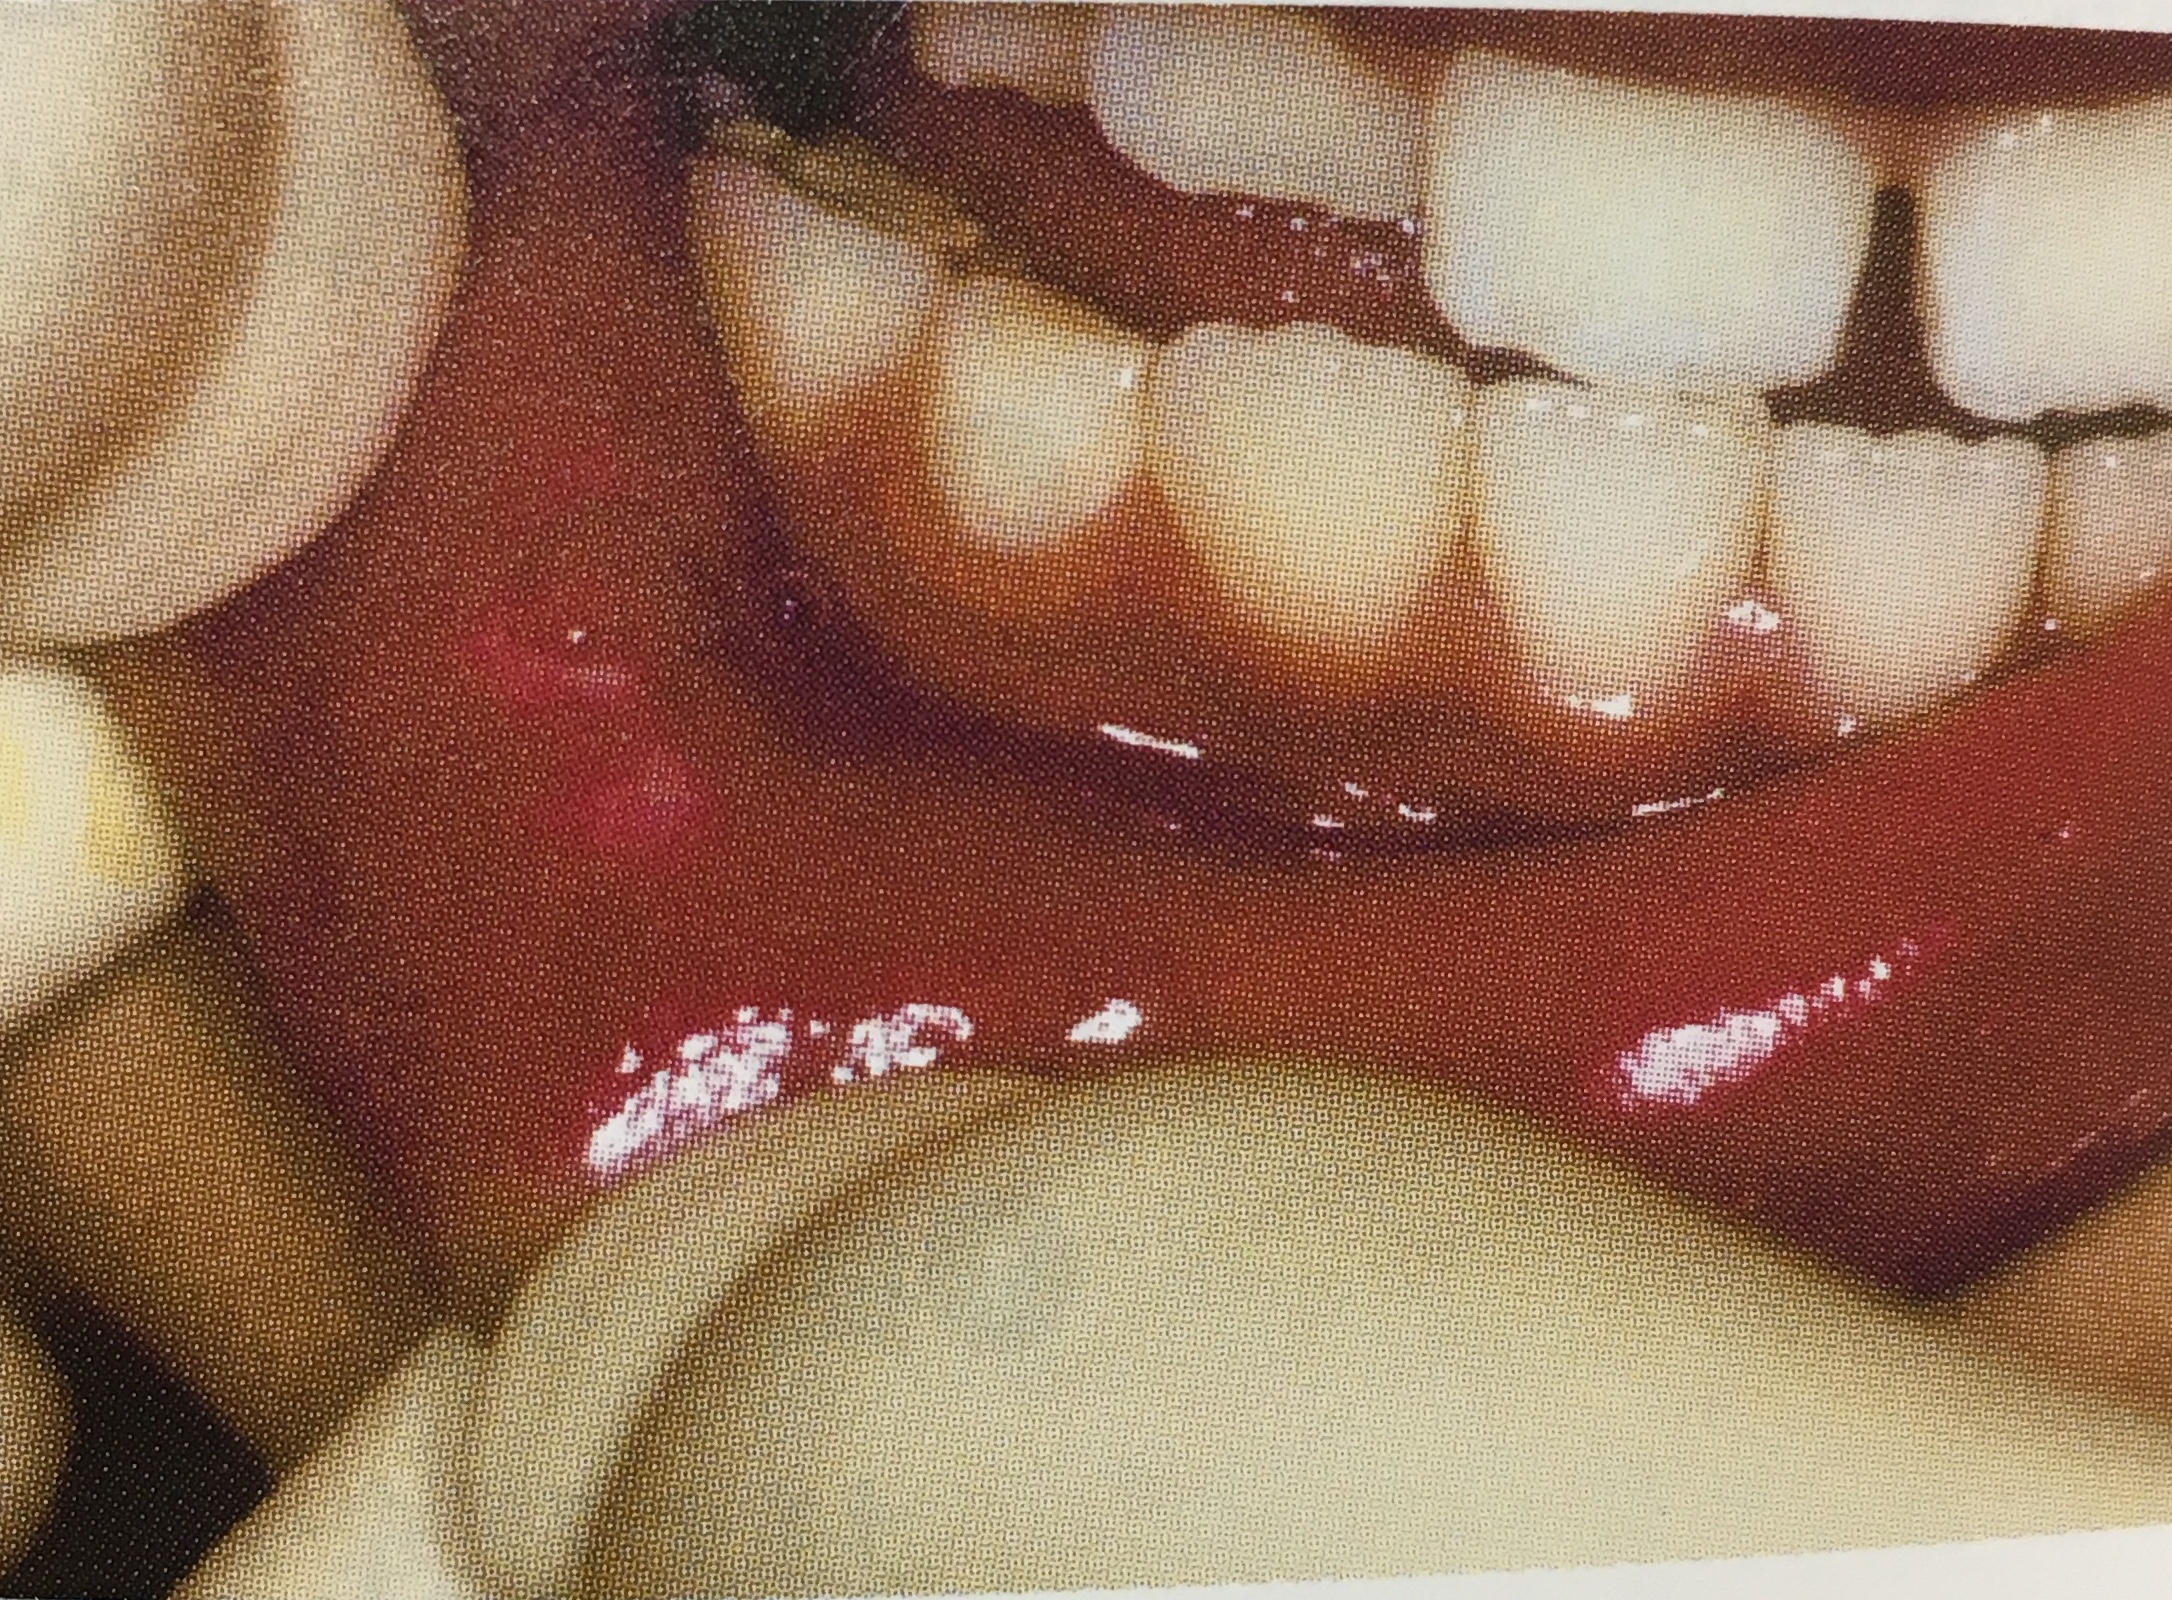

参考までに、麻酔がきれる前に

唇を噛んでしまった様子です。

唇をめくったところに傷ができていますね。

大人の方ですと、ある程度ご自身で噛まない

ようにできますが、お子さんですと

気づいたらこのように傷になっている場合が

あります😭💦

麻酔をしたあと1〜2時間程度は

注意しましょう。